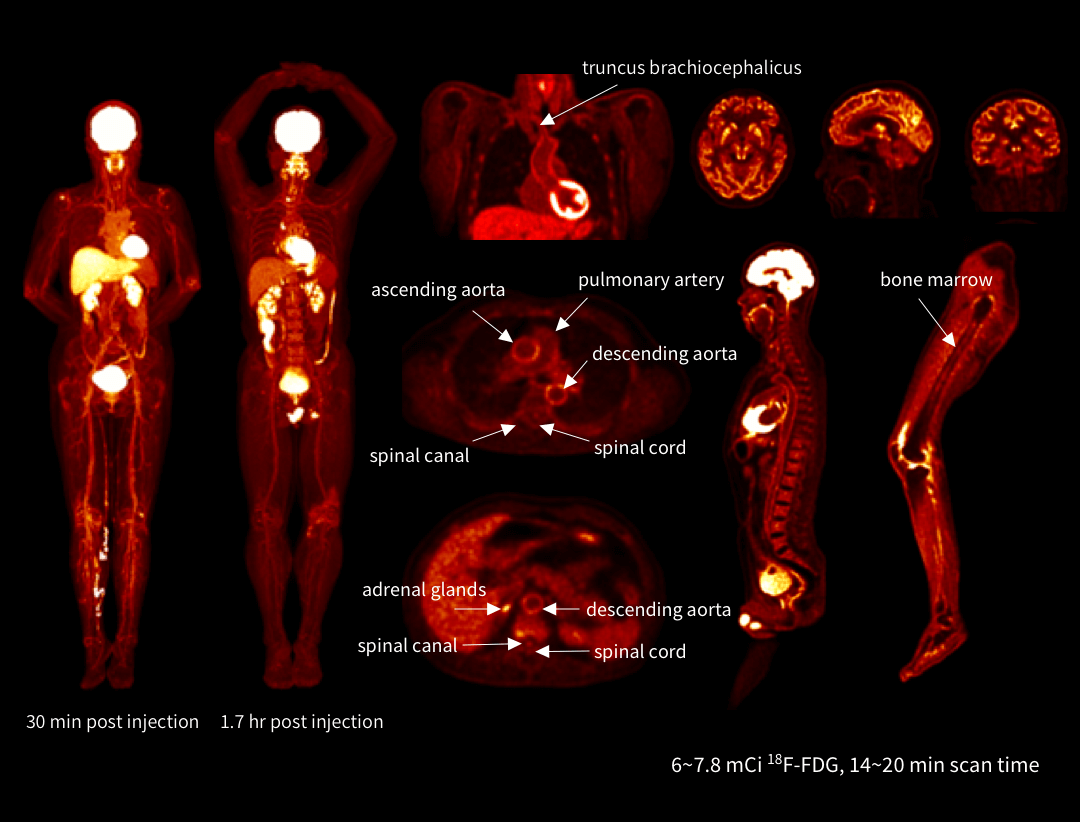

Imagini funcționale cu detalii anatomice

uEXPLORER oferă imagini PET/CT cu rezoluție ultra-înaltă și sensibilitate excepțională. Statisticile de numărare ridicate permit reconstrucția voxelilor mici, asigurând detalii clare și diagnostic precis.

Imagistică dinamică total-body dintr-o singură poziționare

uEXPLORER oferă vizualizarea clară a distribuției radiotrasorului în întregul corp – sânge, organe și țesuturi – pe parcursul timpului. Această capacitate unică permite monitorizare detaliată și analiză clinică precisă dintr-o singură scanare.